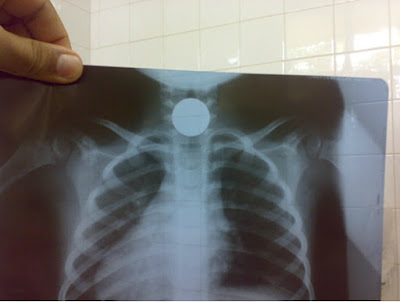

No norte do Estado do Piauí, mais precisamente na Ilha Grande /PI(cerca de 15 KM de Parnaíba) ocorreu que uma criança de aproximadamente três anos de idade engoliu uma moeda que impedia ela de ingerir comida. As pressas a família a levou aos cuidados dos médicos no hospital Dirceu Arcoverde em Parnaíba (PI), mas o procedimento cirúrgico não era custeado pelo SUS.

A família humilde apresentou o problema para alguns médicos em Parnaíba (PI), que cobraram mais de dois mil reais para o procedimento cirúrgico, sem ter condições e com o caso requerendo urgência, resolveram levar a criança às pressas para Teresina com a esperança de que algum médico tivesse a sensibilidade ou realizasse algum procedimento mais simples para solução do problema.

A secretaria de saúde do município de Ilha Grande conseguiu um veículo que levou a criança com urgência até um médico da capital que só precisou usar uma pince para retirar a moeda que ameaçava a vida da garota, agora bem. O caso chamou atenção da família, que não tinha conhecimento de como a medicina mudava tanto em poucos quilômetros e que agora vai redobrar os cuidados e atenção com a criança